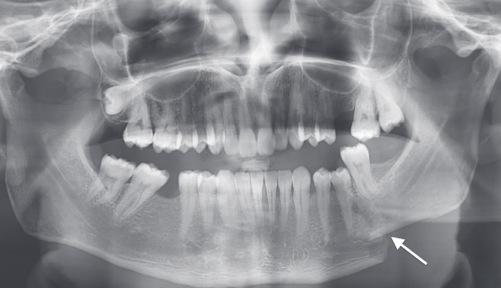

Localisations

- Condyle et Col ++

- Processus coronoide

- Branche montante

- Angle

- Branche horizontale

- Symphyse

- Processus alvéolaire

Fracture de la mandibule